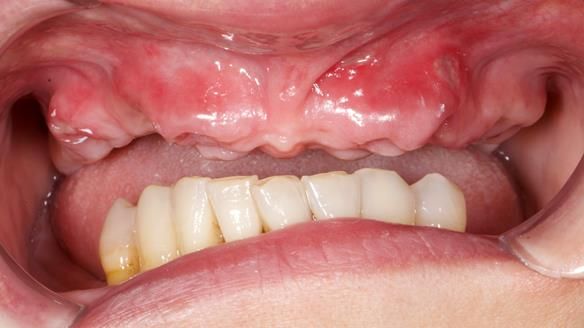

She had previously suffered from generalised periodontitis – stage IV, grade C, currently stable, with reduced attachment across the upper arch.

By the time she came to me, her periodontal condition was stable — but the aesthetics in the upper jaw were very poor.

We provided her with an immediate upper denture (Mk 1), followed by a definitive metal-based upper denture (Mk 2). A lower removable partial denture was discussed, to be made only if needed once the upper treatment was complete. However, at review, this wasn’t necessary — Adnana had excellent neuromuscular control and function, even with a shortened dental arch (SDA).